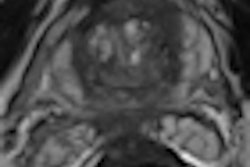

For the procedure, the interventional radiologist makes a small incision in the groin and guides a catheter to the prostate artery. Microscopic beads are released into the artery, where they lodge and temporarily block blood flow to the prostate, causing it to shrink. Several trials of PAE are underway in the U.S.